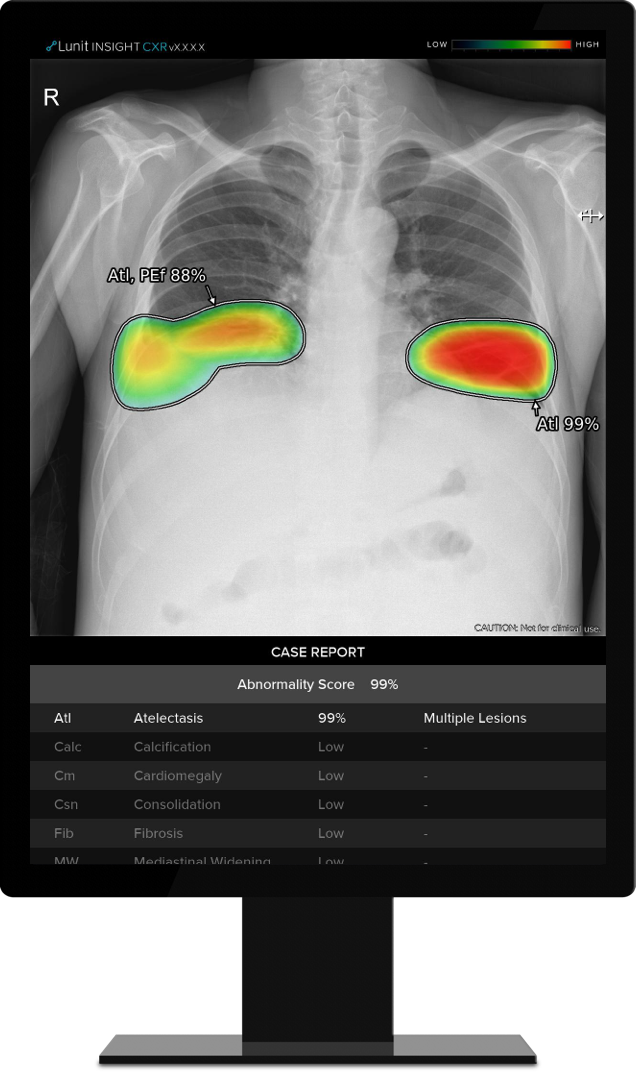

루닛과 미국 하버드 의과대학 매사추세츠종합병원 합동 연구팀은 지난해 4월부터 11월까지 폐렴, 폐결절, 흉수, 기흉 등 4가지 주요 폐 질환과 그 외 다양한 폐 질환이 관찰되는 총 497건의 흉부 엑스선에 대해 루닛 인사이트 CXR을 적용, 판독의 정확성과 효율성을 측정했다.

그 결과 루닛 인사이트 CXR의 주요 폐 질환에 대한 질병 검출 정확도는 평균 89%로, 영상의학과 전문의의 평균 진단율 73%에 비해 크게 높았다. 또한 AI 활용 시 판독 시간이 10% 단축되는 것으로 나타났다.

연구를 주도한 마누딥 칼라 매사추세츠종합병원 영상의학과 교수는 "이번 연구가 갖는 의미는 흉부 엑스레이 영상 판독에 AI를 사용하면 주요 폐 질환에 대한 검출 정확도와 판독 효율성이 개선된다는 것"이라고 설명했다.